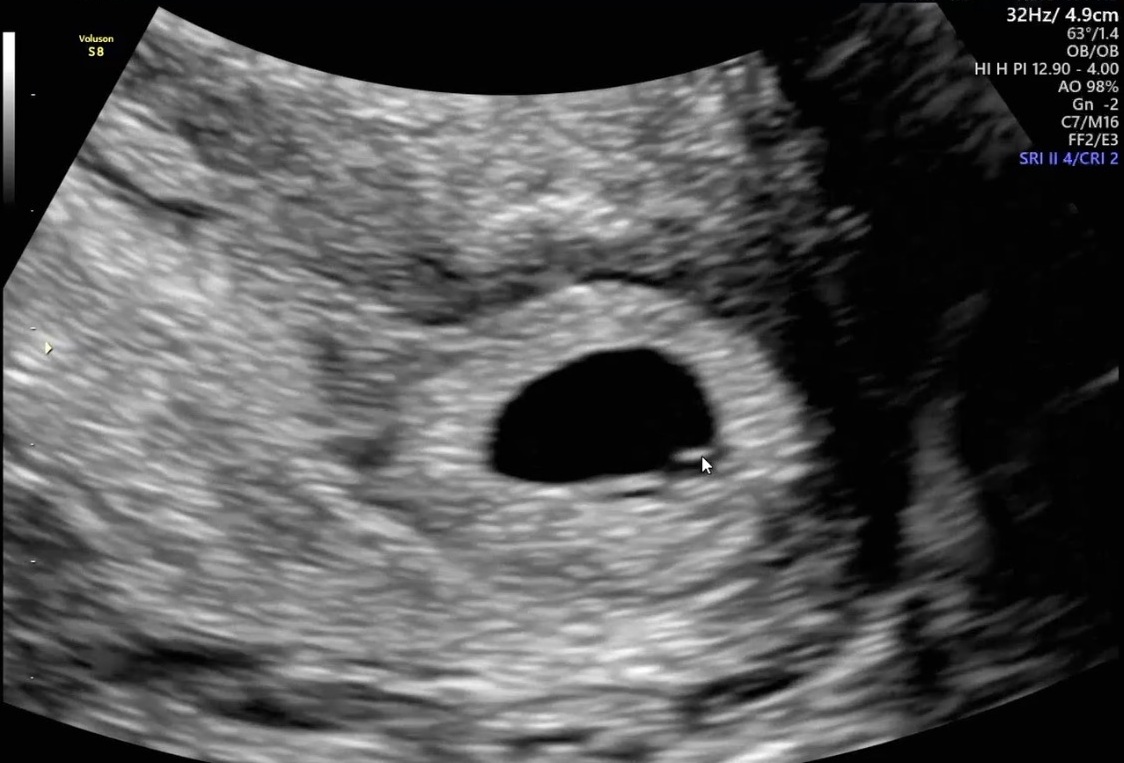

| 가슴 떨리는 임신 이야기를 공유해 주세요. | 시험관 1차는 ‘로또’라는 말을 많이 들어큰 기대를 하지 않고 시작했는데, 꿈만 같아요 임신에 성공하게 되었습니다. |

| 치료 도중 느꼈던 가장 기뻤던 순간과 절망적인 것들은 무엇인가요? 잊지 못할 경험이 있나요? | 피검사 수치를 확인하면서 임신이 확실해졌을 때 가장 큰 기쁨을 느꼈습니다. |